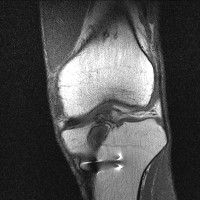

무릎 mri 간단히 봐주실 수 있으시나요 ㅠㅠ

안녕하세요 8년전 십자인대 수술하고 최근 무리한 운동에 무릎 불편감이 생겨서

mri 찍었습니다.

진단결과는 첫 찍은 병원에서 활액막염 이라는 진단을 받았습니다. 혹시 봐주실 수 있으실까요?

올라온 MRI가 단편적이라서 정확한 진단에 어려움이 있지만 십자인대에는 큰 이상이 있지는 않은것 같으며, 무릎관절내 물이 있는 것으로 보아 활액막염의 진단이 맞을 것 같습니다.

하지만 단편적인 영상이기 때문에 촬영병원에서 정확한 판독지 등을 받으시는 것이 좋겠습니다.